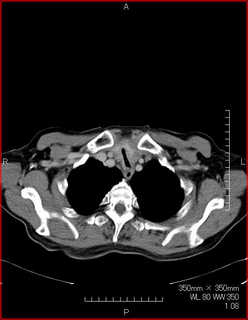

CTで見ると…

3Dだと、こうなります。

気管狭窄ですね。こういう所見もレントゲンで捉えることができるのです。